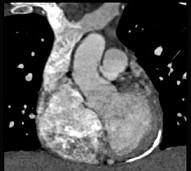

男性45岁,心悸气促乏力,下肢肿胀半年余,曾患肺结核,胸部CT扫描如图所示,请选择正确的选项为 ( )A、X线、CT为常用检查方法B、...

相关内容:男性,气促,下肢,半年,曾患,肺结核,胸部,扫描,如图,选项,常用,检查,方法